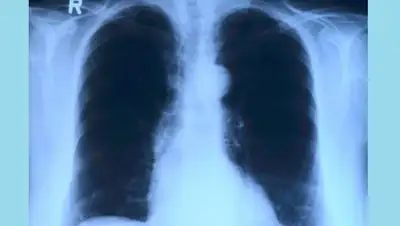

Что нужно знать о раке легких

Не секрет, что рак легких среди всех онкологических заболеваний является одним из самых распространенных. По официальным данным, в Казахстане он занимает 2-е место по заболеваемости и 1-е место по смертности.